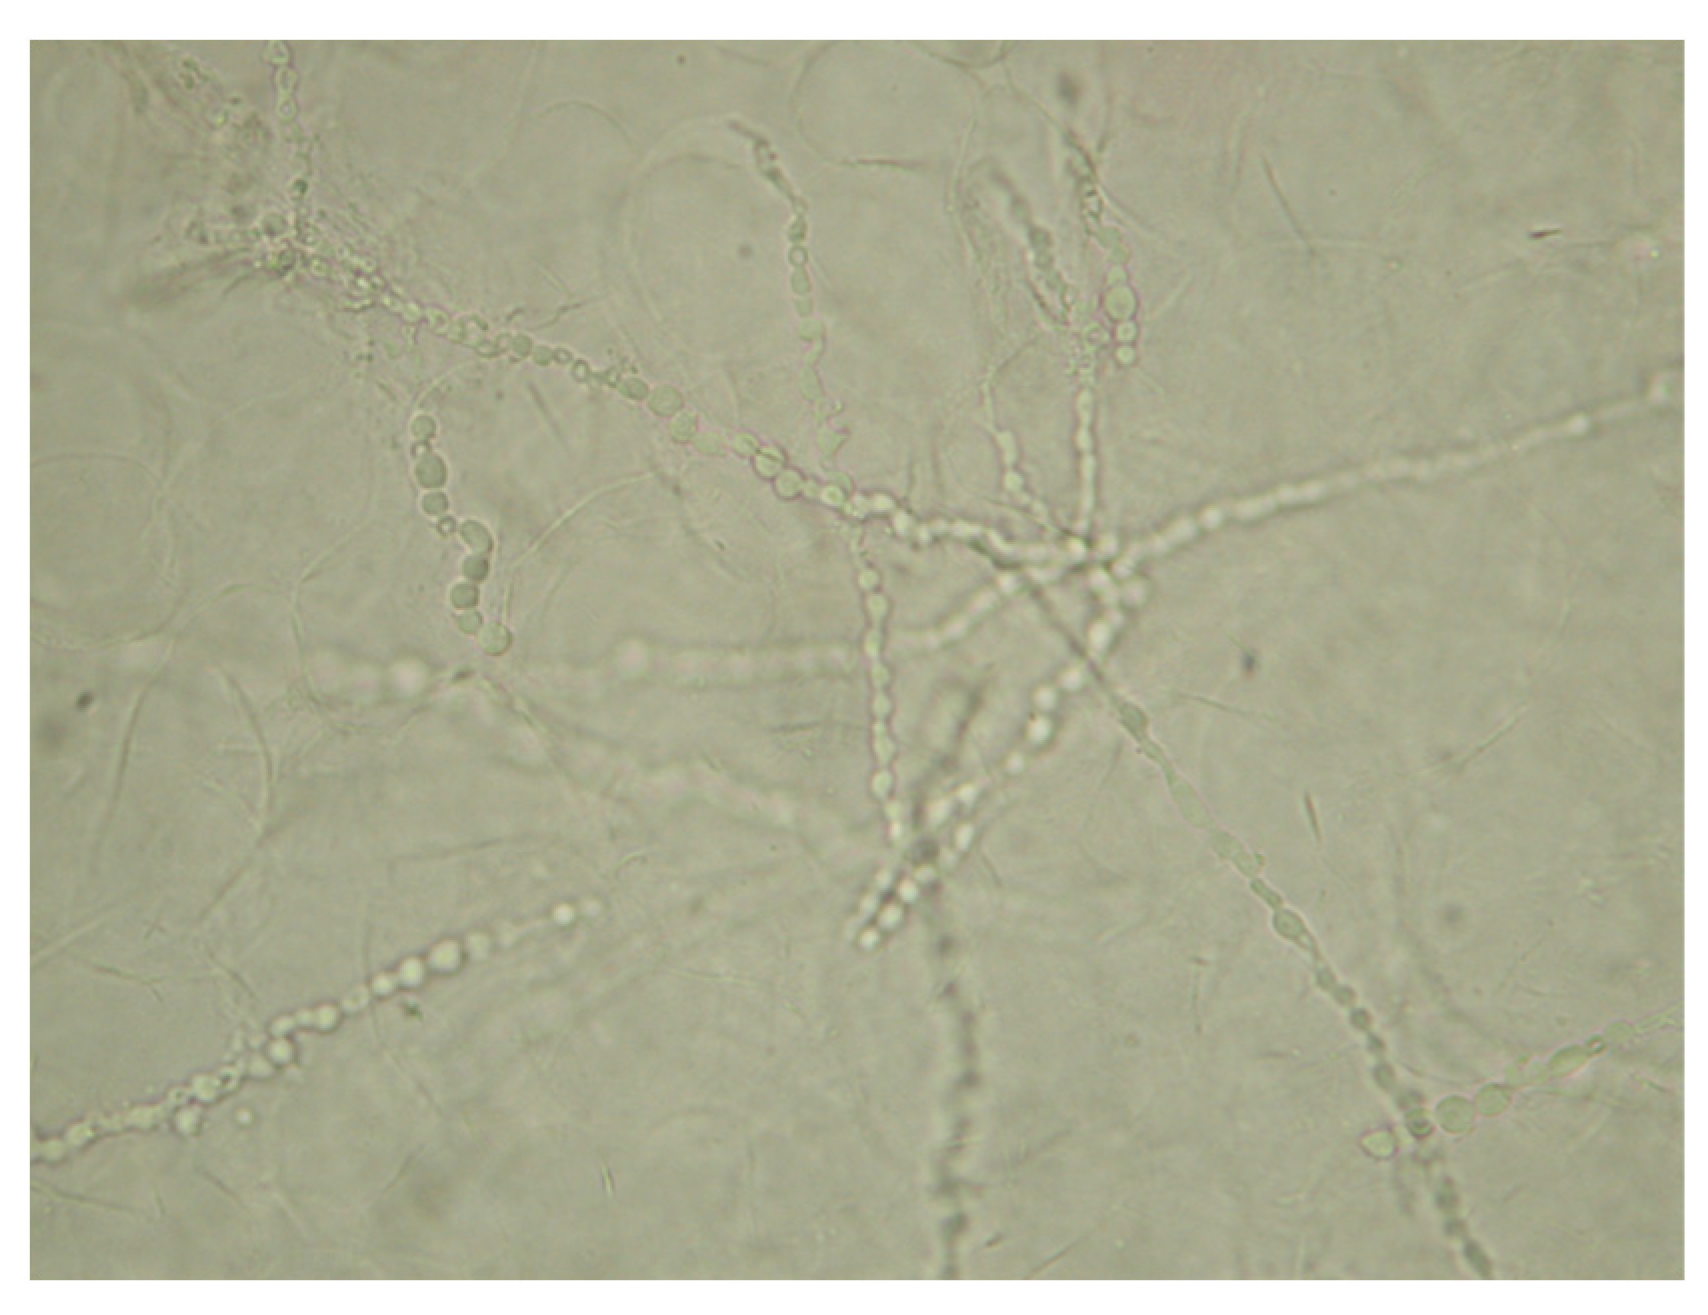

A direct microscopic examination of the samples revealed typical septate hyphae of dermatophytes (Figure 6).

Figure 6.

20% KOH direct microscopic examination (400×). Dermatophyte-typical septate hyphae.